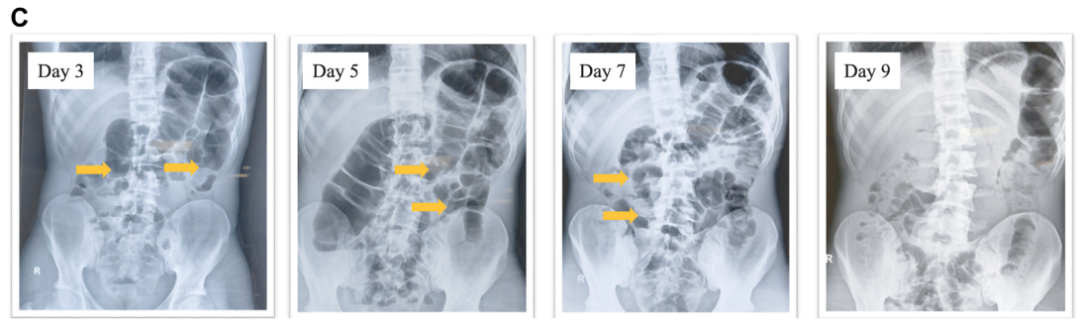

病史摘要:患者为 36 岁男性,主诉持续性腹痛 5 个月,伴黏液血便 1 个月,后进展为不完全性肠梗阻。3 年前确诊急性 B 淋巴细胞白血病,并行异基因造血干细胞移植,移植后发生累及口腔及皮肤的急性移植物抗宿主病,使用环孢素、芦可替尼治疗至腹痛发作。 诊疗过程:实验室检查示 D - 二聚体及超敏 C 反应蛋白升高,其余正常。结肠镜见乙状结肠及直肠黏膜充血等改变,CT